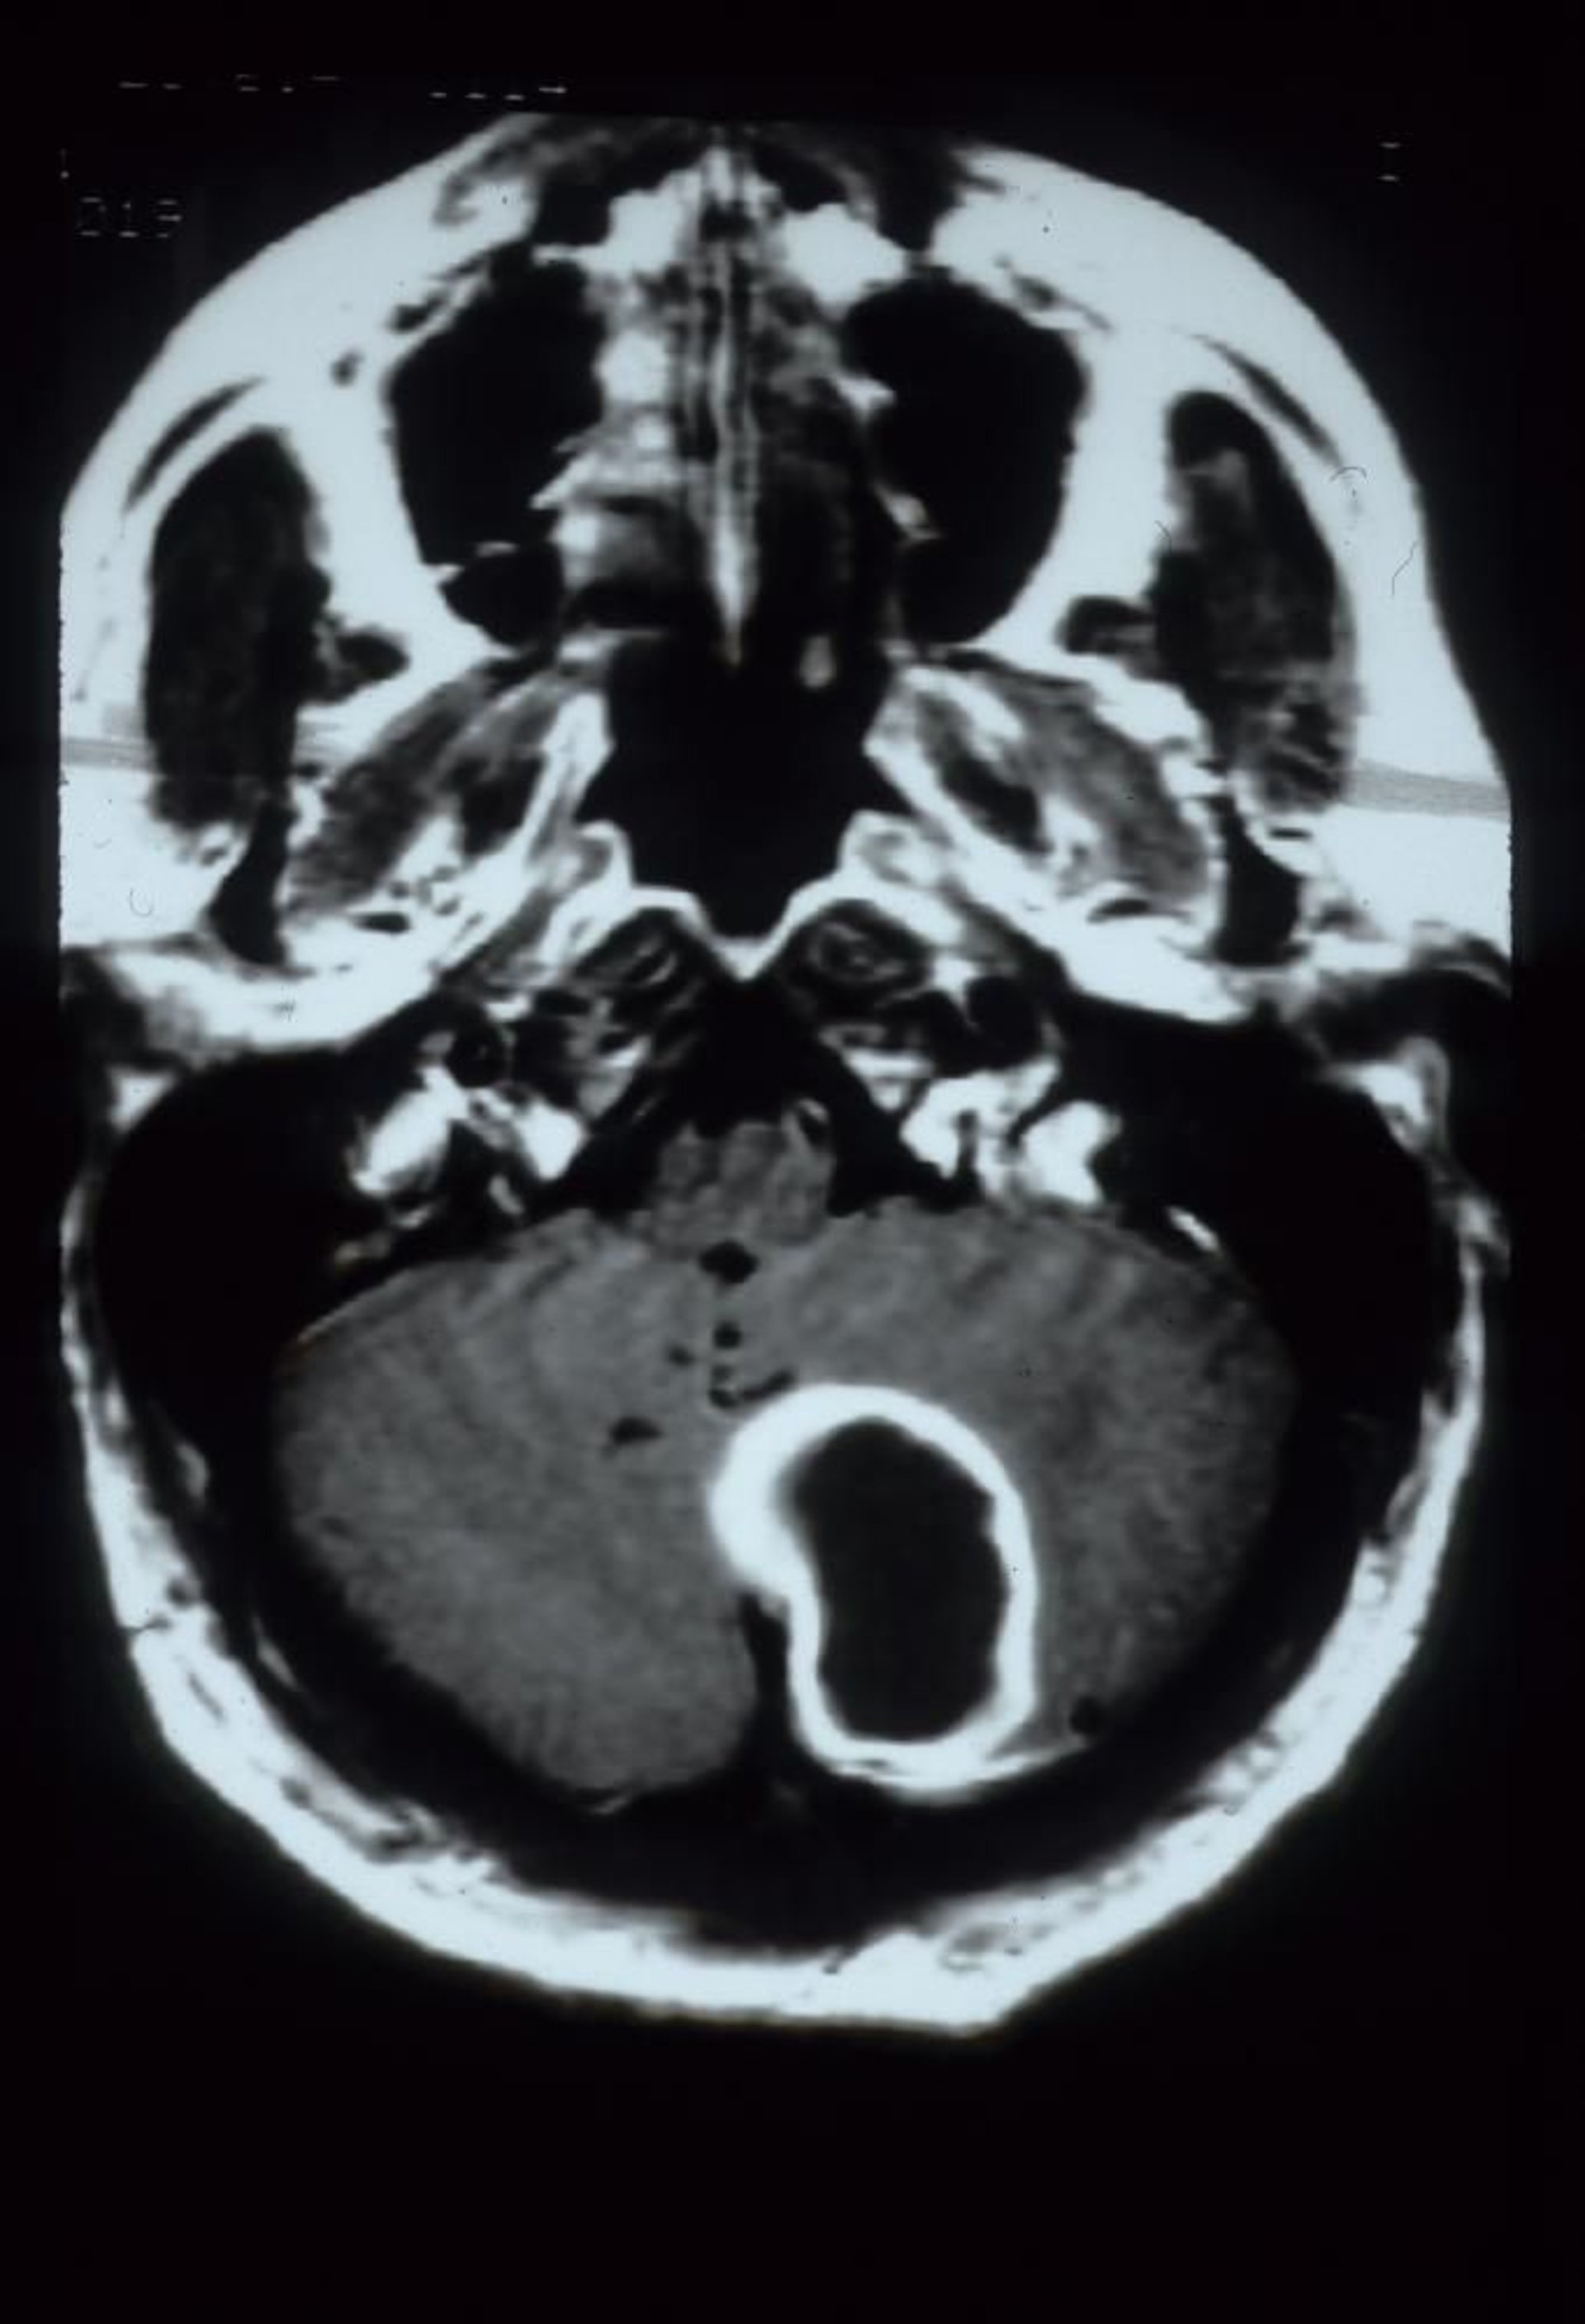

Absceso cerebeloso

Esta RM con gadolinio muestra un absceso cerebeloso, que aparece como una gran lesión cavitaria con refuerzo en el reborde en el hemisferio cerebeloso izquierdo.

Courtesy of John E. Greenlee, MD.